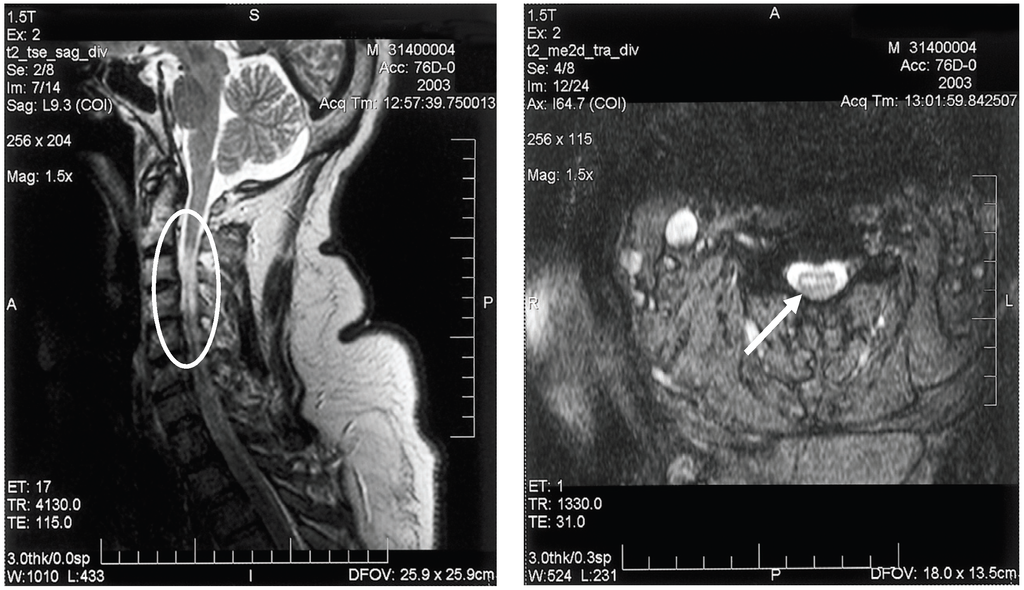

Electrodiagnostic studies (electromyography/nerve conduction studies) will display findings consistent with a motor axonopathy with little or no demyelinating changes and preservation of sensory nerve potentials [49,50]. Spinal MRI may show signal abnormalities in the anterior spinal cord, consistent with anterior horn cell damage; ventral nerve root enhancement may be seen, as well (Figure 3).

Figure 3. Sagittal (A) and axial (B) T2-weighted magnetic resonance imaging of the cervical spinal cord of a patient with bilateral upper extremity paralysis and respiratory failure from West Nile poliomyelitis, displaying the increased signal in the anterior spinal cord (circle and arrow).